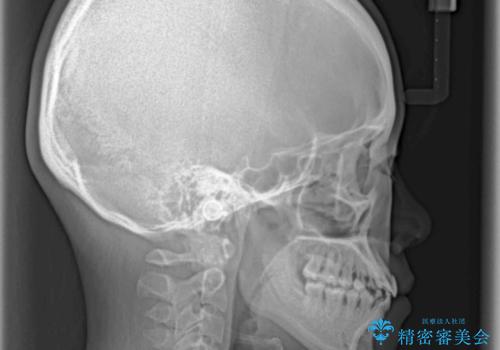

ハーフリンガル 反対咬合の改善

- 前歯の反対咬合を気にして来院された患者様です。

目立ちにくい装置での治療をご希望とのことで、上顎が裏側装置、下顎が表側装置のハーフリンガルにより矯正治療を行うこととしました。

下顎の歯列全体を後方に動かす場合、さまざまリスクを伴うため慎重に行う必要があり、さらには移動量に限界があるため、治療計画は無理のないものとしなければなりません。

下顎左右の奥にアンカーボルトを使用して、無理のない範囲で後方に移動させ、きれいに仕上げることができました。